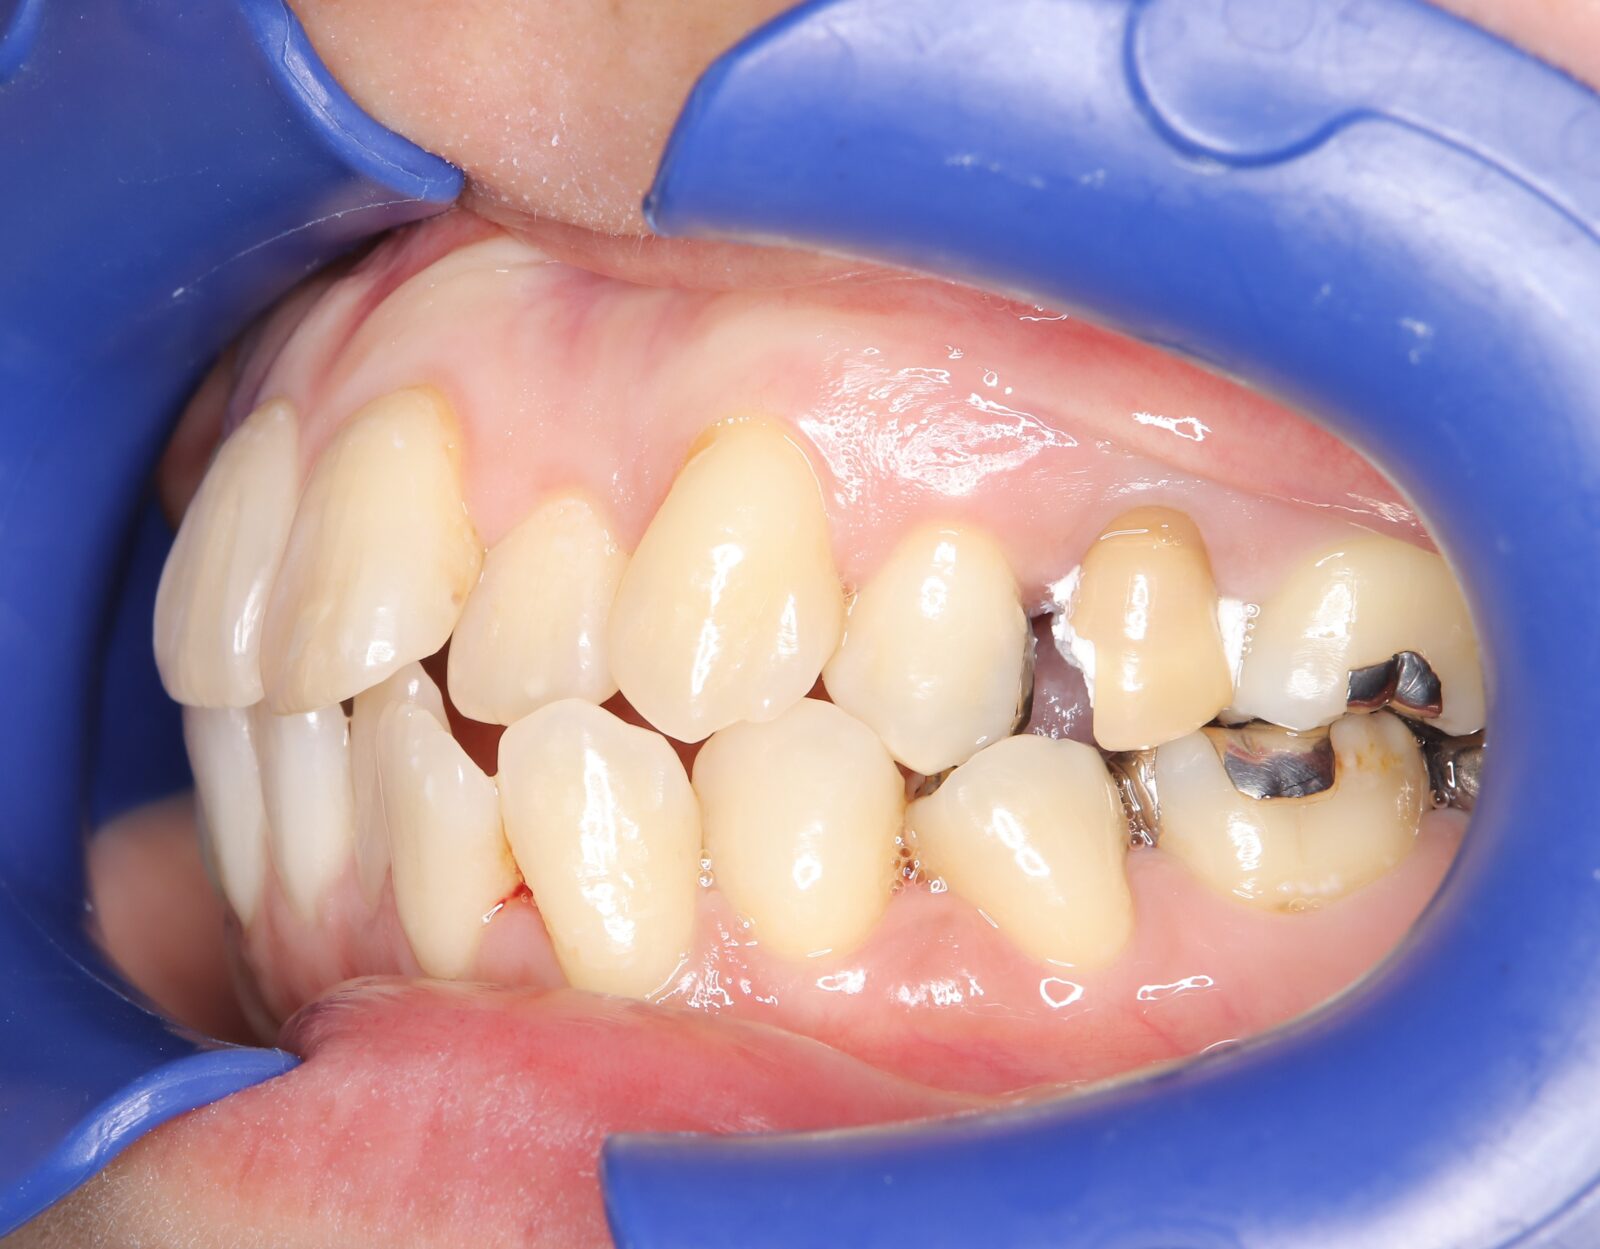

補綴+マウスピース矯正+ホワイトニングの症例

主訴:左上の奥歯が欠けた(40代女性)

臼歯部と前歯のクロスバイト。左右の顎の動きは制限されていた。

口腔顔貌精密検査、

精密根管治療、(仮歯+ファイバーコア+ジルコニアクラウン)×2本、インビザラインフル+補助装置、リテーナー

140万円(税別)

別途:デュアルホワイトニング、歯周初期治療、定期メンテナンス

期間:2年